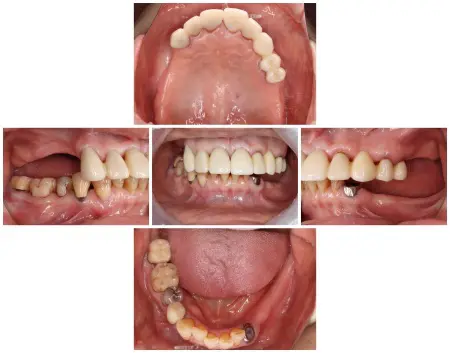

患者様は1991年より来院されており、10年前には右上前歯から左上奥歯までの8本分を連結した被せ物「フルジルコニアブリッジ」で治療していました。(治療前画像の2枚目)

拝見したところ、上下ともに取り外し式の部分入れ歯が装着されていましたが、下顎には状態が悪く温存できない歯が3本あり、噛み合わせの高さがずれる「フレアアウト」も見られました。

患者様の場合もフレアアウトを放置した結果、上顎のフルジルコニアブリッジが前方に突出し、上下の部分入れ歯も外れやすくなり、しっかり噛むことが難しくなったと考えられました。

再び食べ物をしっかり噛めるようにするには、崩れた歯並びや噛み合わせを整える治療と、外れやすい上下の入れ歯も作り直す必要があると診断しました。

上顎はフルジルコニアブリッジ部分が前方に出ており、このままだと噛み合わせを整えることが難しいため、ブリッジを外して総入れ歯にする治療の必要性を説明しました。